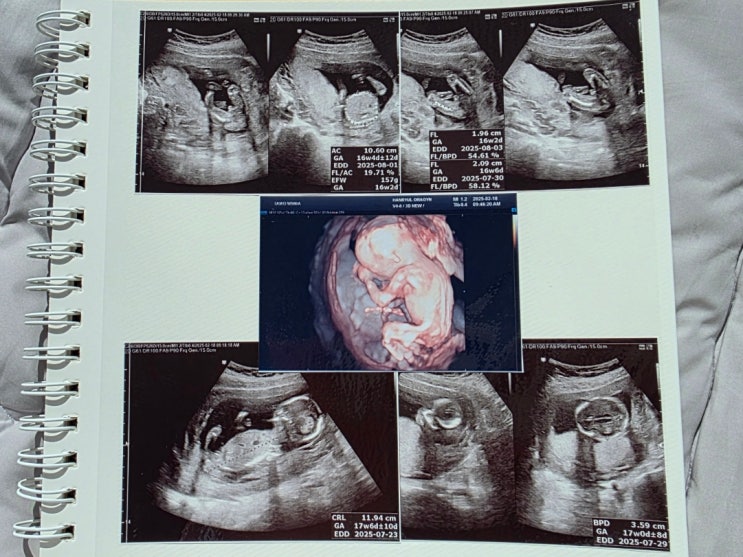

2월 17일 ~ 2월 23일 진료 전에 초콜릿 먹으면 애기가 잘 논다고 해서 진료 보기 전에 초콜릿 먹음 초콜릿 ...